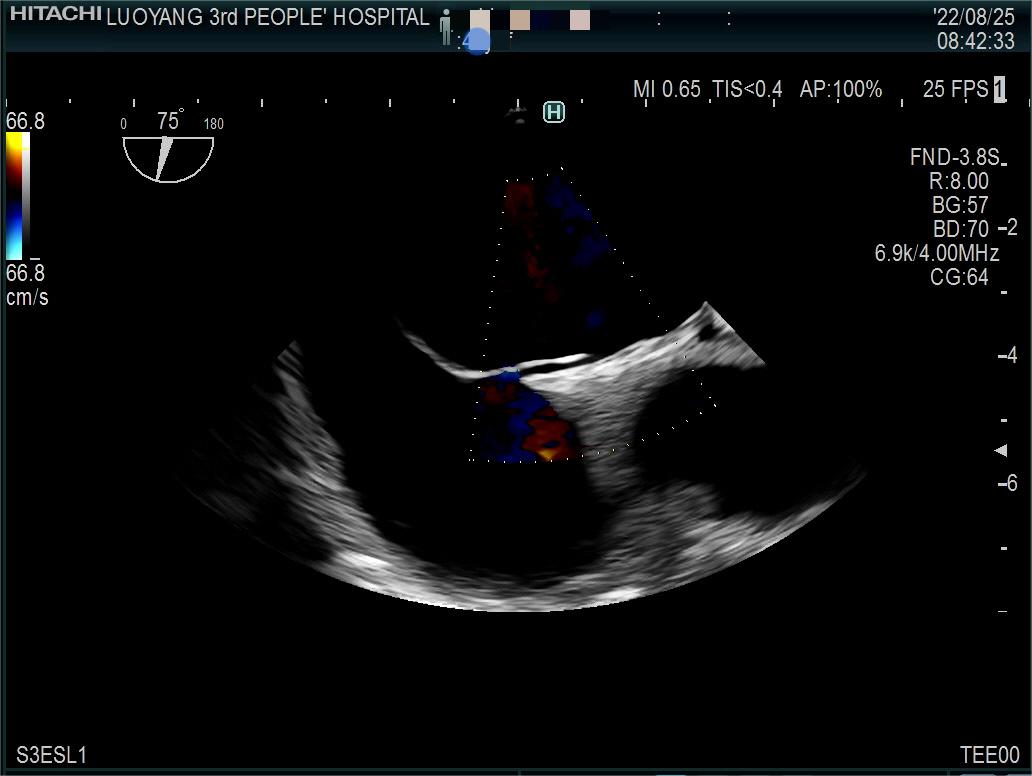

8月25日,经过我院超声科积极筹备,相关科室的大力配合下,我院首例经食道心脏超声检查顺利开展。

据了解,经食管超声心动图检查是将超声探头插入食管,直接贴在心脏的后方,从后向前观察心脏、血管和血流动力学情况,避免了气体及脂肪的干扰。由于食道超声的探头频率高于普通经胸超声探头,可以扩大心脏的扫描范围,提高图像质量及细微分辨率。与经胸超声心动图相比,经食管超声心动图具有距心脏近、软组织影响少,避免了胸骨和肺组织干扰,能充分显示左、右心房,房间隔,心耳,肺静脉和主动脉等优点,能更加准确地诊断心脏细小病变及疑难疾病。特别是能明确因卵圆孔未闭导致的偏头痛及矛盾性栓塞患者的病因、并能有效评估房颤患者是否有血栓形成的危险性,为后续治疗提供可依据。